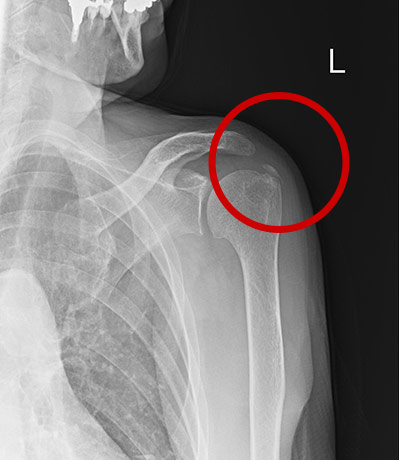

きっかけなく左肩痛

通常の正面撮影では異常は見当たらず

写っているそれぞれの骨の形状や位置関係が正常であることは確認できるが、痛みの原因特定には至らない画像

棘上筋が骨に付着する箇所が見えるよう姿勢調整し撮影

棘上筋腱に隠れていた

石灰沈着を描出

診断:石灰性腱炎